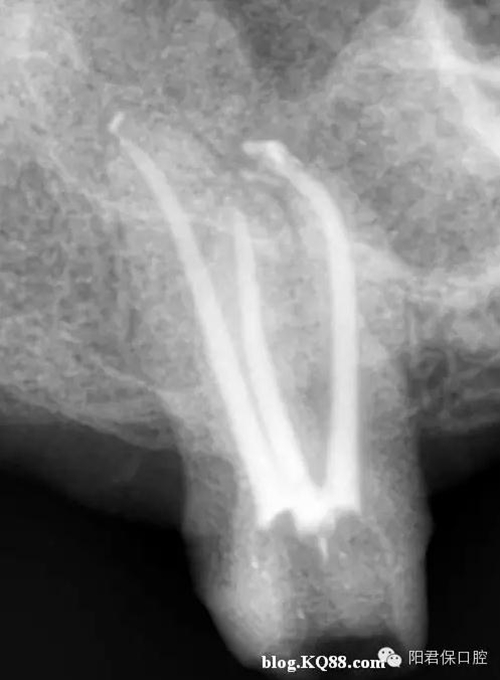

患者:姜XX 性別;女 年齡:65 根據(jù)齲壞程度、患者的癥狀、修復(fù)需要,且對(duì)收費(fèi)及牙髓處理均征得同意后第一次行右下4、5,左下4、5、6;第二次行左下2,右下2 ,右上7一次性根管治療術(shù)。

術(shù)后見右下4,左下4均有側(cè)支充填,且位置對(duì)稱,左下6近中根中部有側(cè)支;左下5、左下6遠(yuǎn)中根管均多個(gè)開口。

熱牙膠垂直加壓后有封閉劑和牙膠超填,但無(wú)術(shù)后反應(yīng)。